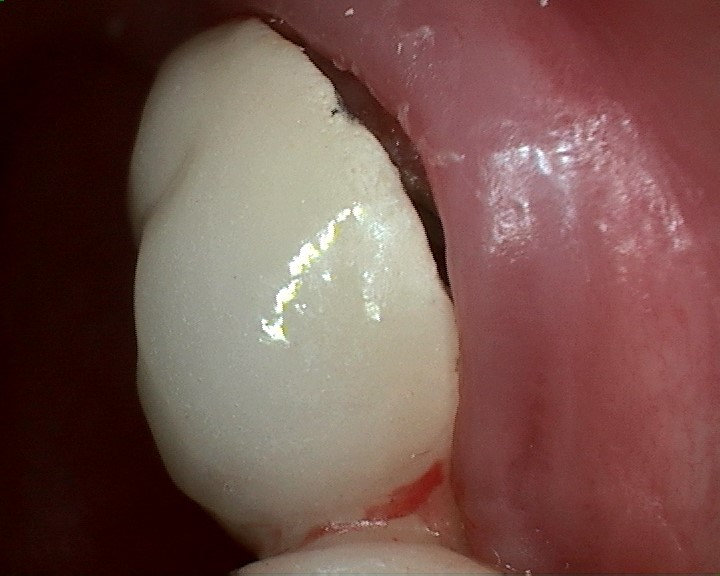

Amalgam Replacement

Replaces bad amalgam fillings with a tooth-like material. Restores the tooth to its original look. No red gum and trapping of food particles anymore. It provides a better appearance and better function.

Amalgam replacement with Cerec Onlay.